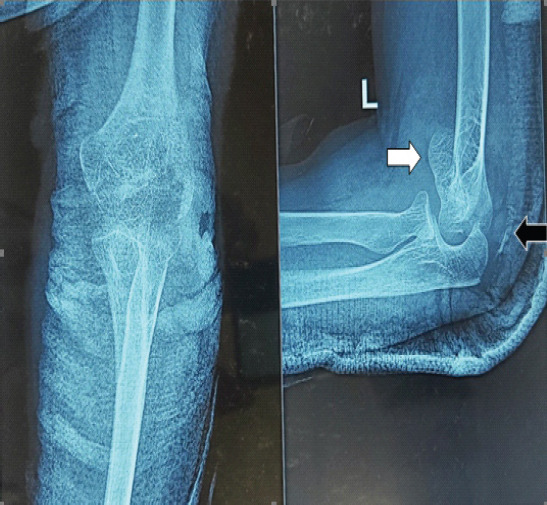

Case report: We present a distinctive case in which an entire capitellum and trochlea were fractured as a single unit in the coronal plane (mimicking McKee type 4 capitellum fractures), along with a DTTA injury in a female patient in her late 40s. This injury was treated using open reduction and internal fixation with cannulated cancellous screws, along with the repair of the DTTA injury.